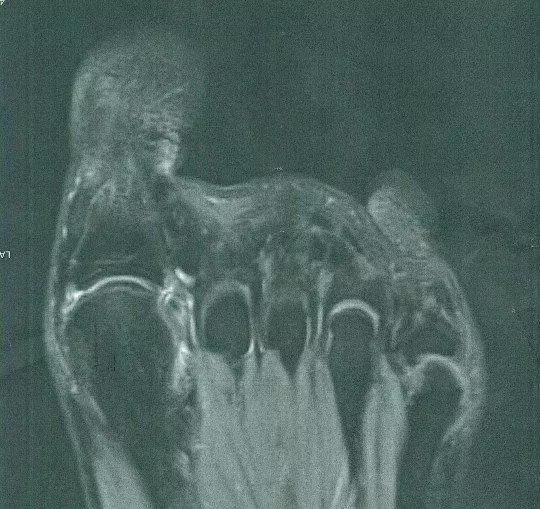

可是天妒英才的事情还是发生了,虽然她的名气一再的飙升,但是她的身体状况却一日不如一日。在秀场上不断地摔倒和常年穿着高跟鞋导致猪妹的脚部问题越来越严重。在微博上晒出脚部检查的图像后引起了粉丝的心疼。于是,在被医生告知再也不能穿高跟鞋的她,宣布退役。暂时告别这个让她热爱让她成名的舞台。粉丝们也纷纷表示让猪妹好好养身体。